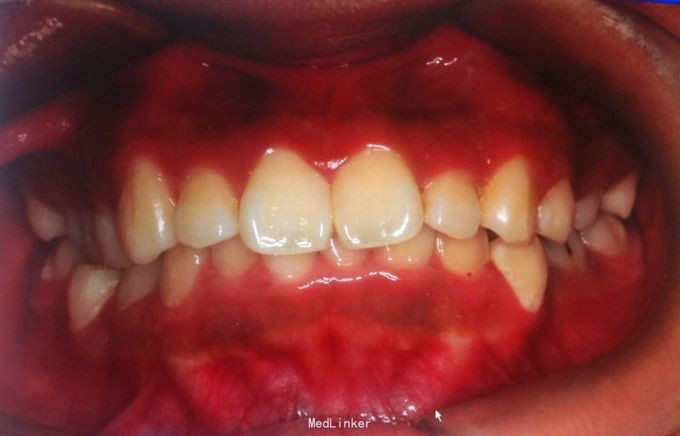

恒牙期 左侧磨牙中性关系,右侧远中关系 前牙三度深覆合 上合牙列中度拥挤,下颌重度拥挤 下颌中线偏右 关节有弹响

安氏二类,牙列拥挤 拔牙矫治,拔除14、24、34、44,强支抗,排齐整平上下牙列,矫治后磨牙中性关系,前牙覆合覆盖正常,面型略改善